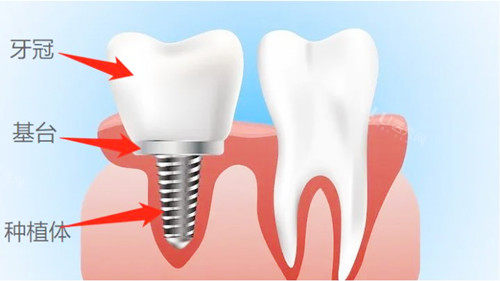

一、种植牙项目

国产种植牙:4380元起/颗

韩国登腾种植牙:5800元起/颗

韩国奥齿泰种植牙:6500元起/颗

美国皓圣种植牙:8500元起/颗

瑞士ITI种植牙:11800元起/颗

瑞典诺贝尔种植牙:10800元起/颗